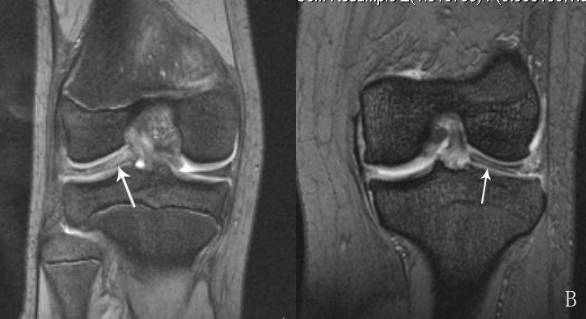

4、桶柄状撕裂

为纵形撕裂伴碎片向内侧移位,这种移位的片段类似于桶的柄,该型撕裂几乎累及半月板的所有部位,常易漏诊,在 MRI 上可以有多种表现,主要为半月板的宽度减小,在通过半月板体部的冠状面上未见到与对侧半月板共同构成的蝶形表现,同时可见到内移的半月板碎片位于髁间窝或交叉韧带旁,可形成双前、后交叉韧带征,这一征象在诊断半月板桶柄状撕裂中有重要意义;